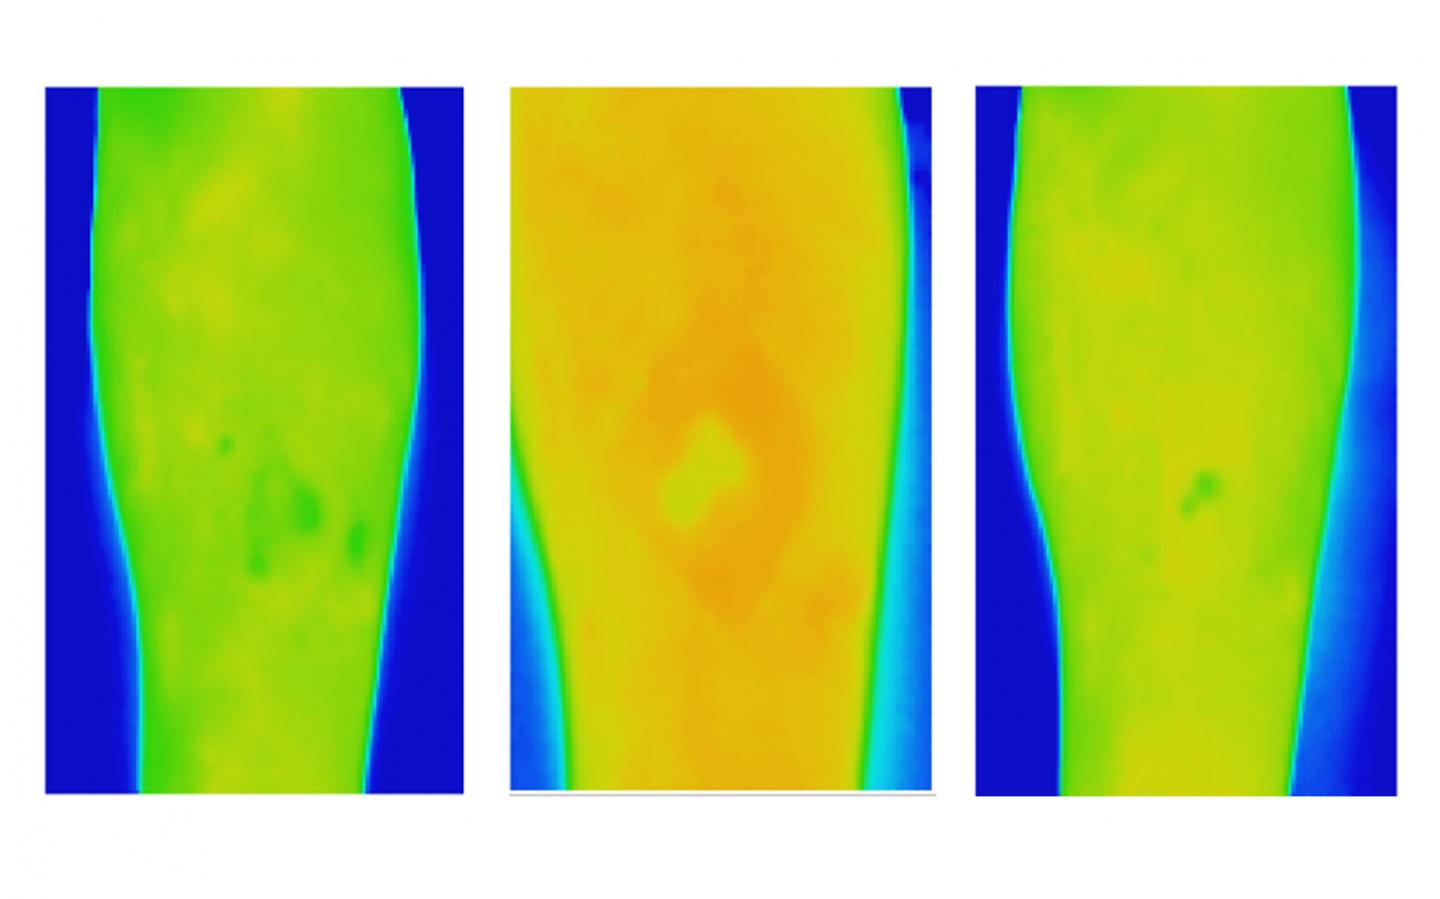

image: Thermal images of a venous leg ulcer showing healthy healing progress over three weeks.

The Australian study shows textural analysis of thermal images of venous leg ulcers (VLUs) can detect whether a wound needs extra management as early as week two for clients receiving treatment at home.

Researchers found the method, which provides information on spatial heat distribution in a wound, could accurately predict whether VLUs would heal in 12 weeks by the second week after baseline assessment.

This is because wounds change significantly over the healing trajectory, with higher temperatures signalling potential inflammation or infection while lower temperatures can indicate a slower healing rate due to decreased oxygen in the region.